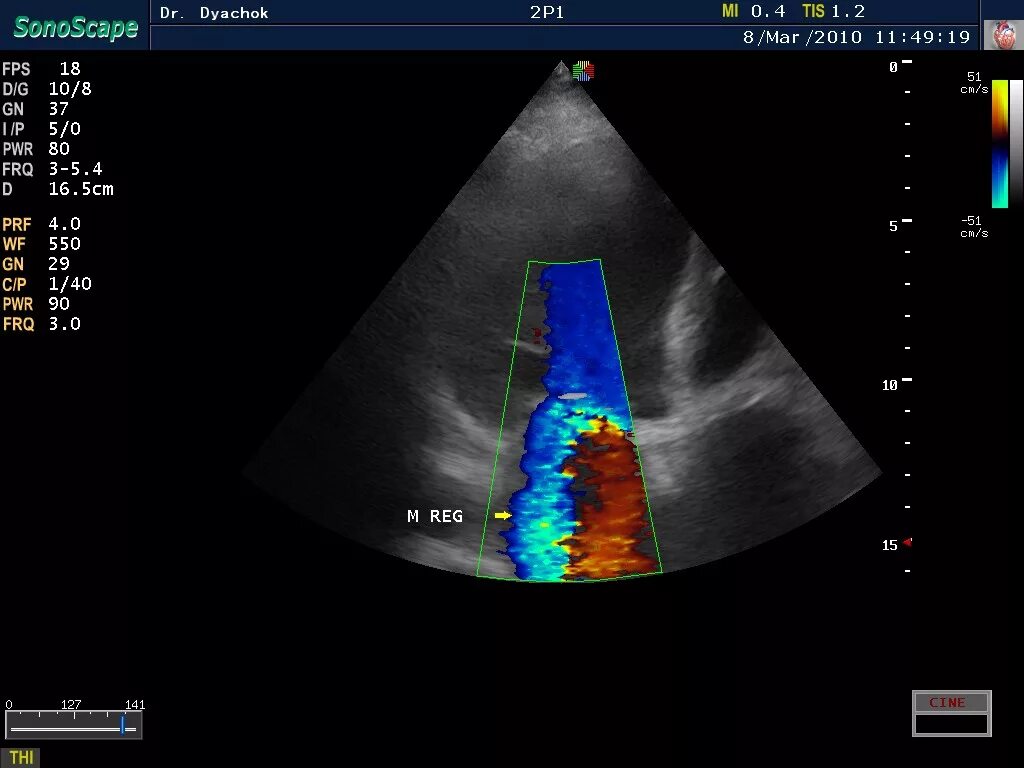

Режимы узи аппарата